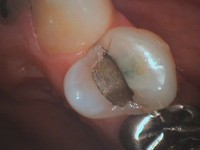

アマルガム充填された歯です。

アマルガム充填の辺縁も欠けて段差になっているのがわかります。

ここから虫歯が進行します。